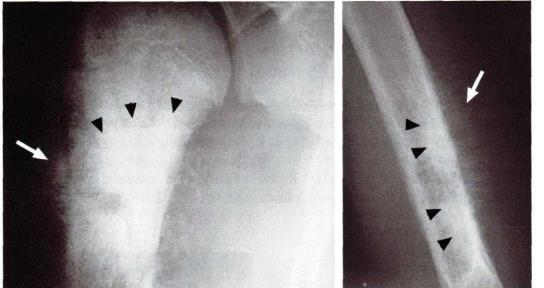

Analise a radiografia, abaixo:

Reação periosteal em pacientes com osteossarcoma do úmero (setas). A maior densidade radiográfica na metáfise e diáfise umeral está relacionada com a matriz óssea da lesão (pontas de setas).